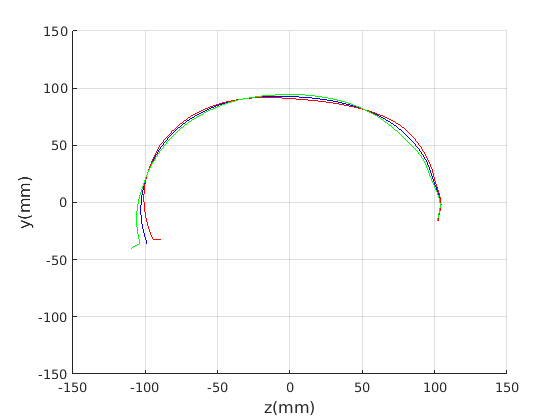

Figure 16 shows examples of the robust ellipse fit for four head profiles. The centre of the ellipse is used in a pose normalisation procedure where the ellipse centre is used as the origin of the profile and the angle from the ellipse centre to the nasion is fixed at -10 degrees. We call this Ellipse Centre - Nasion (ECN) pose normalisation and later compare this to GPA. The major and minor axes of the extracted ellipses are plotted as red and green lines respectively in Fig. 16.

|

Figure 17 shows all 100 profiles overlaid with the same alignment scheme. The median value of major ellipse axis and the ellipse centre-nasion angle differ by 3.6 degrees, so that when the nasion angle is fixed at -10 degrees, the median ellipse angle is -6.4 degrees (cf. -7.4 degrees with manual landmarking of the nasion). We noted regularity in the orientation of the fitted ellipse as is indicated by the clustering of the major (red) and minor (green) axes in Fig. 17 and the histogram of ellipse orientations in Fig. 18. For most people, the major axis of the ellipse is closely aligned with the y-axis (upright), and titled slightly forwards. A minority of heads (9%) in the training sample have their major ellipse axes closer to the vertical (these relatively tall and short heads are known as brachycephalic.) Ellipse axis clustering (relative to the fixed ellipse centre-nasion line) does not appear to be sharply defined. This is because many crania are close to circular in cross-section, making the orientation of these angles sensitive to small changes in shape from one person to the next. Note also the variation at the back of the head due to a variety of hair styles, some of which protrude from under the cap. We limit the region over which we model the cranial shape in order to crop this unwanted data out.